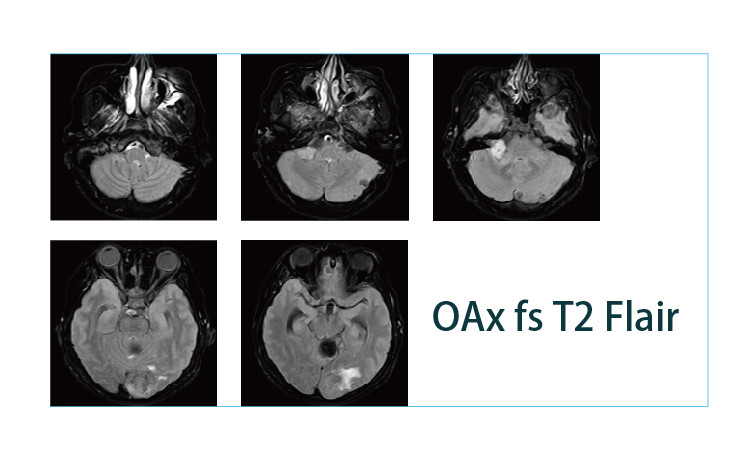

【朗润影像档案】20190412磁共振影像病例结果讨论